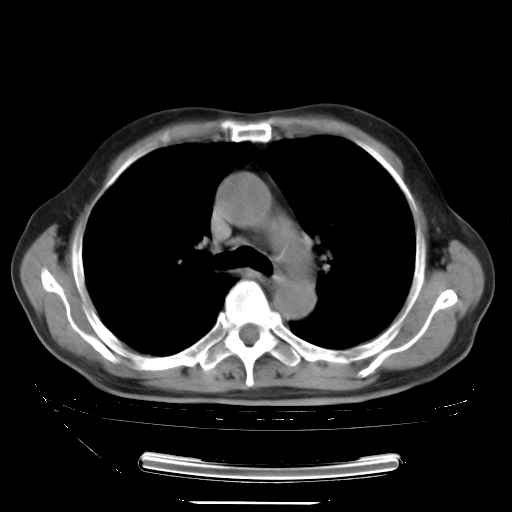

今天复查肺部CT,发现双肺广泛磨玻璃样改变。所以我把3月19日和5月9日相隔50天的肺部CT上传。请大家会诊。

2009年3月19日肺部CT片。

5月9日肺部CT(在4月27日齐鲁医院肺部CT描述部分肺组织磨玻璃样改变,12天后肺组织广泛磨玻璃样改变)

大致读了系列胸部CT:纵隔窗无明显异常,肺窗:从4、27至今:主要是双肺中下野外带可见毛玻璃样改变,目前处于急性肺泡炎阶段,至于原因考虑1、结替组织或胶原血管性疾病所致?2、恶性疾病如恶组在肺部所致的表现或细支气管肺泡癌?3、药物或其它原因如肺蛋白沉着症所致肺泡炎目前不太可能?总之,明天就去请我院的呼吸科、感染科、血液科和临免专家会诊哈。